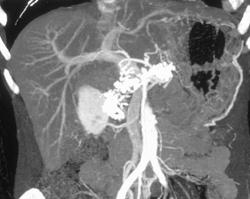

Insulinoma